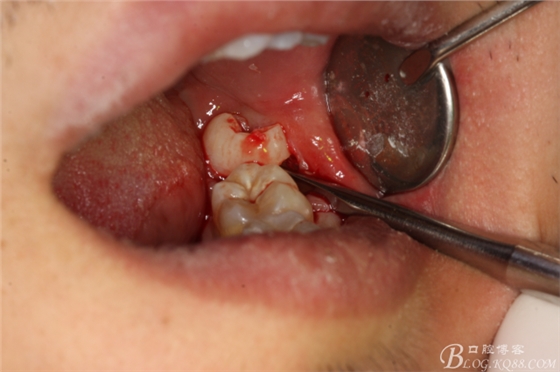

圖16.持針器取出38牙根

圖17.牙根呼之欲出

圖18.牙槽窩幾乎保留原有形狀,棉球壓迫止血,手術(shù)完畢。